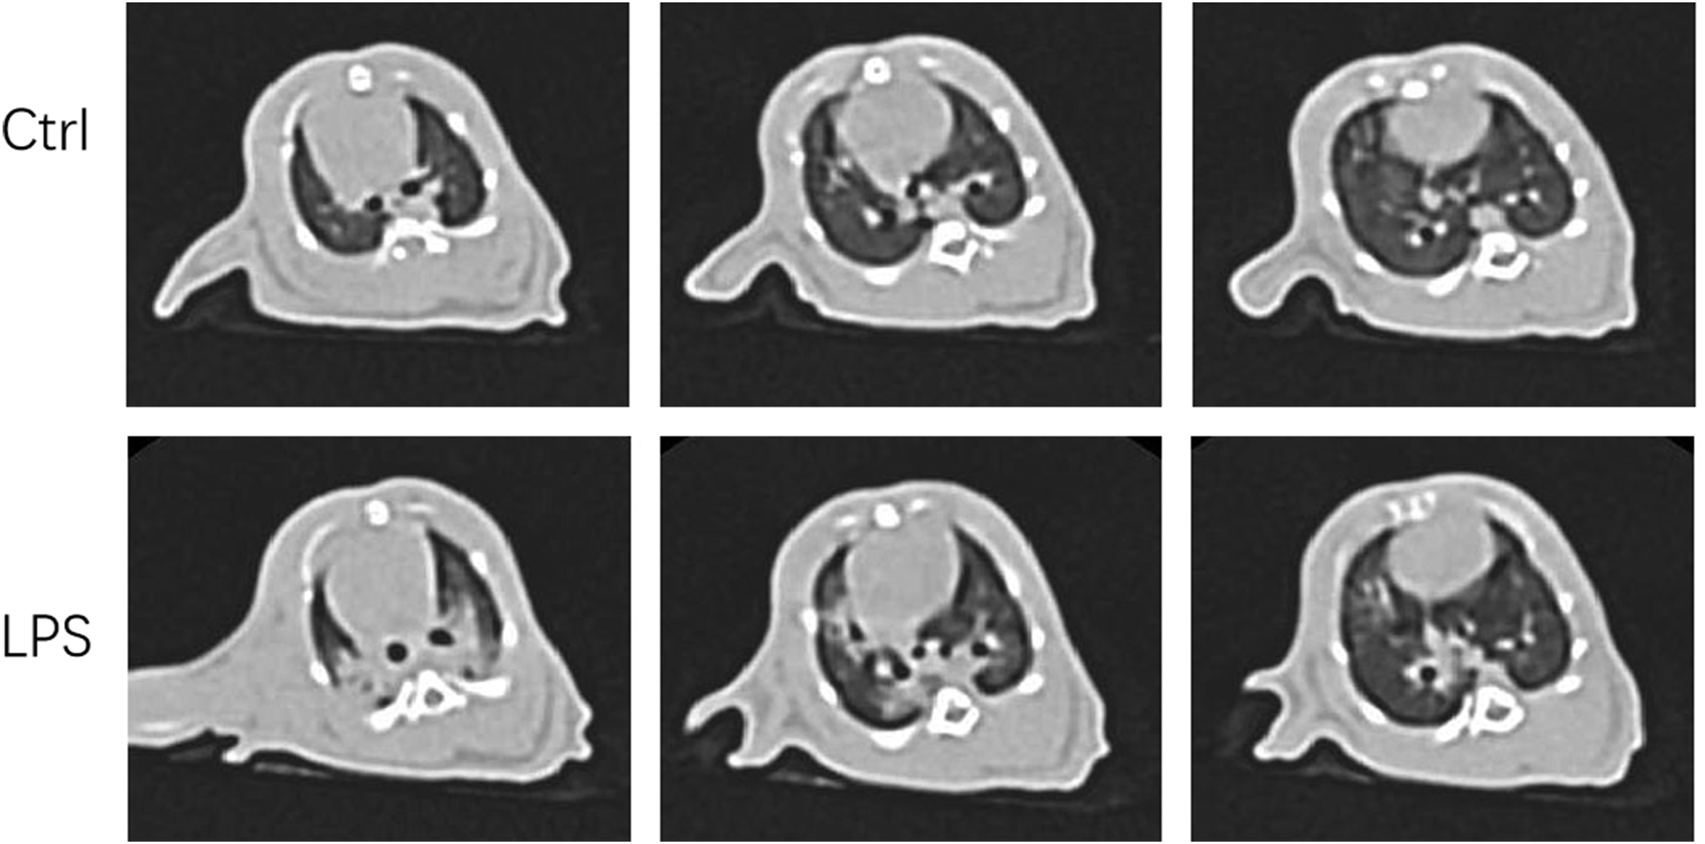

LPS-induced ARDS in rats was confirmed by CT and PaO2/FiO2 analyses

We were eager to know if lung injury by COVID-19 affects platelet biogenesis in the lung. Many reports have confirmed that clinical symptoms, chest imaging, and autopsy in COVID-19 are consistent with the pathological process of ARDS (Ma et al., 2020) (Gibson et al., 2020). The ARDS model induced by LPS was used as a substitute for viral challenge because of the biosafety limit. To confirm that the model was successfully established, lung CT was applied. After injection of LPS (20 μg/g body weight) after 12 h, the rats underwent CT scan every 2 hours. At 16 h, lung images of the LPS-induced ARDS group presented blurred and messy bilateral lung markings, multiple consolidation, and patchy shadows with blurry margins (Figure 2), which indicated establishment of the ARDS model. At 24 h, the PaO2/FiO2 was significantly decreased in LPS-induced ARDS group (Supplementary Figure S1).

FIGURE 2

Computer tomography images of LPS-induced ARDS rats and controls. Chest computed tomography was performed in rats induced by LPS or saline (control). Images demonstrate one representative animal per group and were viewed at the same window width (2000 HU) and window level (−500 HU).